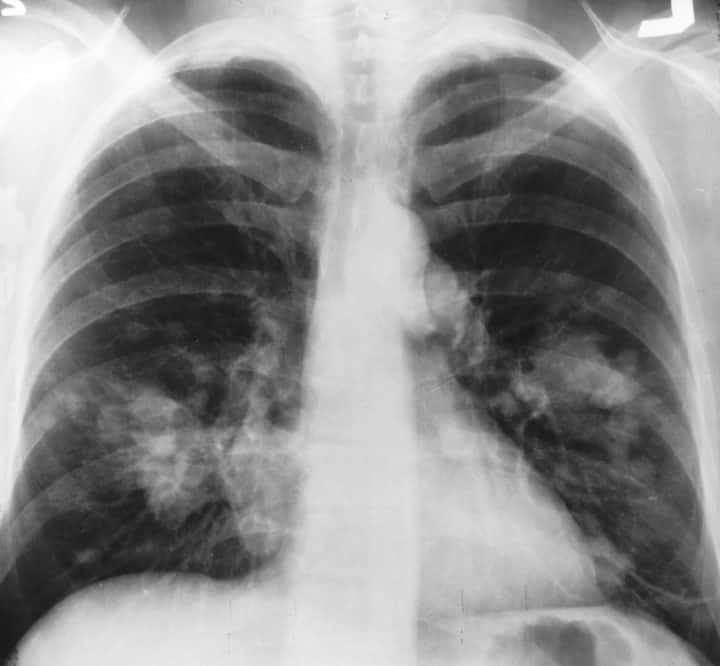

Dans une autre étude publiée  dans la revue « Nature Medicine »Google est venu renforcer cette promesse de dépistage, cette fois-ci au niveau du cancer du poumon. Un projet de recherche de la filiale d’Alphabet s’est penché sur l’utilisation de l’IA dans le dépistage du cancer du poumon. Il a conclu que certains algorithmes peuvent être plus efficaces que des radiologues dans la détection de ce cancer.

poumon

Pour ce faire des chercheurs et ingénieurs de Google ont entraîné un algorithme de machine learning sur une base de 45 856 scanners thoraciques. L’algorithme génère alors un modèle 3D du scanner puis y recherche des tissus malins dans les nodules pulmonaires qui normalement sont difficilement vus à l’œil nu, d’autant que les radiologues se penchent généralement sur des images en 2D. L’algorithme génère enfin une estimation de la malignité du cancer du poumon. Il peut également s’appuyer sur des données issues de scanners précédents.

Par la suite, les chercheurs ont comparé les résultats à ceux de six radiologues certifiés. Résultat: l’algorithme a détecté 5% de plus de cas de cancer du poumon et a réduit les faux positifs de plus de 11%.